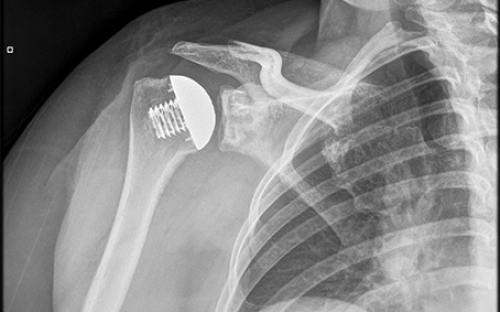

Bei einer Schulterrevision handelt es sich um den Wechsel einer bereits bestehenden Schulterprothese. In einem erneuten Eingriff wird diese teilweise oder vollständig entfernt und durch ein neues Implantat ersetzt. Ein Tausch der Schulterprothese ist dann notwendig, wenn das eingesetzte Implantat Schmerzen und erneute Bewegungseinschränkungen bereitet.

Eine Schulterprothese besteht meist aus Metall- und Kunststoffkomponenten, die sich durch natürliche Belastung und Bewegung über die Zeit abnutzen. Auch wenn das Material grundsätzlich sehr langlebig sind, lässt sich ein langfristiger Verschleiß nicht verhindern. Der Abrieb kann zu kleinen Partikeln im Gelenk führen, die das Gewebe reizen oder eine Entzündungsreaktion hervorrufen. Betroffene klagen dann über Schmerzen und Bewegungseinschränkungen im Arm.

Auch wenn die Komplikationsrate bei der Implantation einer Schulterprothese mit unter 10 % recht gering ist, kann sich die Prothese nach einiger Zeit lockern. Dabei löst sich die Verbindung zum Knochen und es kommt zu Instabilität im Gelenk. Weitere Begleiterscheinungen sind zunehmende Schmerzen, die sich oft zunächst nur unter Belastung äußern sowie hör- oder fühlbare Reibegeräusche bei Bewegung.

Die Revision ist ein komplexer Eingriff, der in Vollnarkose durchgeführt wird. Zu Beginn wird die aktuelle Prothese von unseren Schulterspezialisten freigelegt und je nach Zustand teilweise oder vollständig entfernt. Dabei wird festgestellt, in welchem Zustand sich Knochen und Weichteile befinden und anhand dessen entschieden, welcher Prothesentyp als Ersatz infrage kommt.